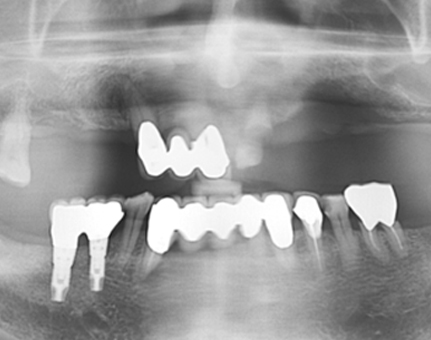

문치과 임플란트 사례

모든 전후 사진은 단순한 비교가 아닌,

환자분의 고민과 변화의 기록입니다.

문치과는 각자의 사연에 맞는 해답을 찾습니다.